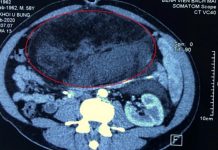

Xơ gan

Gan là một cơ quan có kích thước lớn với bề mặt nhẵn đảm nhiệm rất nhiều chức năng quan trọng của sự sống. Trước hết, gan là nơi lưu trữ và giải phóng các dưỡng chất khi cần; lá gan cũng hỗ trợ cho hoạt động tiêu hóa; tham gia vào việc phân giải các chất có khả năng gây hại cho cơ thể.

Tuy nhiên, lại có nhiều căn bệnh mạn tính có thể gây tổn thương gan, nếu bị tác động trong thời gian dài có thể gây ra tình trạng xơ hóa. Xơ hóa gan xảy ra khi mô sẹo hình thành quá mức. Cụ thể, các protein collagen dạng sợi sẽ thay thế dần mô gan khỏe mạnh. Một trong những nguyên nhân hàng đầu gây ra hiện tượng xơ hóa gan phải kể đến virus viêm gan B hoặc A. Bên cạnh đó, còn có thói quen uống nhiều bia rượu; các bệnh gan nhiễm mỡ do tình trạng béo phì và tiểu đường.

Trong trường hợp chúng ta không có biện pháp xử lý kịp thời và để tình trạng xơ hóa tiếp diễn trầm trọng hơn có thể tiến triển đến xơ gan, lúc này lá gan sẽ trở nên rất cứng và chắc. Đồng thời, lưu lượng máu qua gan sẽ giảm đáng kể, gan cũng gần như mất đi khả năng thực hiện các nhiệm vụ của mình.

Chứng xơ gan hoàn toàn có thể dẫn đến những bệnh lý nghiêm trọng hơn như suy gan và đặc biệt là ung thư gan. Trong thực tế lâm sàng, người ta nhận thấy 70-80% ung thư gan phát triển trên xơ gan.

Vì thế, bác sĩ khuyến cáo khi phát hiện xơ gan cần đến viện điều trị không nên tự điều trị tại nhà bằng phương pháp dân gian sẽ vô tình làm bệnh nặng hơn và không còn khả năng điều trị.